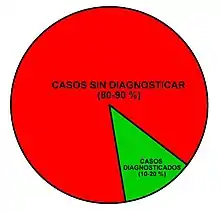

A fecha de 2019, se calcula que la mayoría de los celiacos en la mayoría de los países del mundo nunca llega a recibir un diagnóstico.[65] Esto es debido al escaso conocimiento sobre la celiaquía existente entre los profesionales de la salud, incluyendo médicos de cabecera, pediatras, gastroenterólogos y especialistas en general,[65][17][12][66] y a las dificultades del diagnóstico.[65][27][41][67] Cinco de cada seis celíacos (aproximadamente el 83 %) permanece sin diagnosticar.[42] En los niños, las cifras llegan a alcanzar el 90 %.[68] En aquellos que consiguen ser diagnosticados, el tiempo transcurrido desde el comienzo de los síntomas es habitualmente muy prolongado, con retrasos diagnósticos que pueden oscilar entre los siete y los cincuenta y nueve años,[69] período durante el que los pacientes acuden a repetidas consultas de diversos especialistas, los cuales por lo general, no piensan que la celiaquía pueda ser la enfermedad que causa sus diversas molestias.[70][71][72][73] No existe ninguna prueba que por sí sola pueda descartar la enfermedad celíaca.[27][74] Una gran parte de celiacos son diagnosticados por error como sensibilidad al gluten no celíaca.[40]

La celiaquía es un proceso con una elevada prevalencia mundial, que afecta aproximadamente al 1-2 % de la población general,[18] pero está aún claramente subestimada y, por tanto, insuficientemente diagnosticada.[27] [99] [100] [101] [102] [103] Representa un importante problema de Salud Pública a nivel mundial y es fundamental que exista un mayor conocimiento de las características clínicas de la enfermedad, para que los médicos, tanto generales como de digestivo, pediatras y de otras muchas especialidades, piensen en ella y la diagnostiquen con una mayor frecuencia y lo más precozmente posible.[19] [27] [66]

En España se han realizado diversos estudios epidemiológicos que encuentran hallazgos similares tanto en población general como en donantes de sangre.[27][102][103] En una estimación aproximada, podría haber entre 3,5-4,5 millones de personas afectadas por celiaquía en toda Europa y entre 500 000-900 000 en España, de las que se calcula que en la actualidad solo en torno a un 10-20 % de los casos están realmente diagnosticados.

En el diagnóstico

Pese a que la celiaquía es una de las enfermedades con base genética más frecuentes, con una prevalencia media del 1-2 % en la población general y que puede debutar a cualquier edad de la vida, está claramente subestimada e infradiagnosticada, con aproximadamente un 85 % de los casos sin diagnosticar en la actualidad.[18][42] Existe un escaso conocimiento sobre la enfermedad celíaca entre los profesionales de la salud, que tiende a perpetuarse.[12][66]

Existe la creencia de que los especialistas en enfermedades de los niños son los profesionales que más casos detectan, si bien la realidad es que el anclaje en las ideas clásicas sobre la enfermedad celíaca, la aplicación sistemática de protocolos desfasados, la reticencia a someter a los niños a pruebas invasivas y el miedo a prescribir una dieta “de por vida”, dan como resultado que la mayoría de casos de celiaquía pasen desapercibidos durante la infancia. Las cifras de niños sin diagnosticar llegan a alcanzar el 90 %.[68]